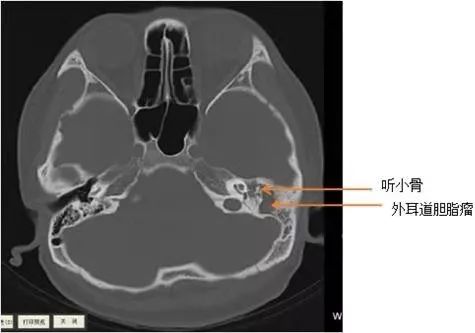

ct片

不出所料,颞骨CT检查显示小林左侧外耳道胆脂瘤,已挤压破坏左侧听骨链,且与左侧颈静脉及面神经管等重要结构关系密切,所以小林疼痛症状明显,左耳听力已有明显的下降。一切明了,小林如释重负。